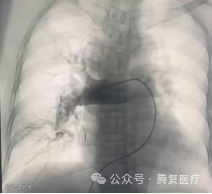

右侧股静脉置管,送⼊ 5F PigtaiL 造影导管⾏双肺动脉造影⽰ : 右下肺动脉主⼲及多肺段均见充盈缺损 ,部分分支闭塞。左肺主⼲及多肺段均见充盈缺损。更换置换 22F ⾎管鞘 , 送⼊ CX20 型号的 Tendvia™抽栓导管⾄于右肺动脉⾎栓近端⾏⾎栓抽吸治疗 , 抽取⼤量红⾊⾎栓。

术前肺动脉造影